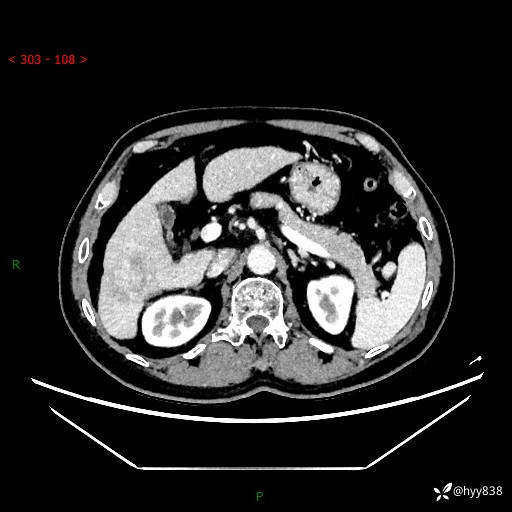

静脉期